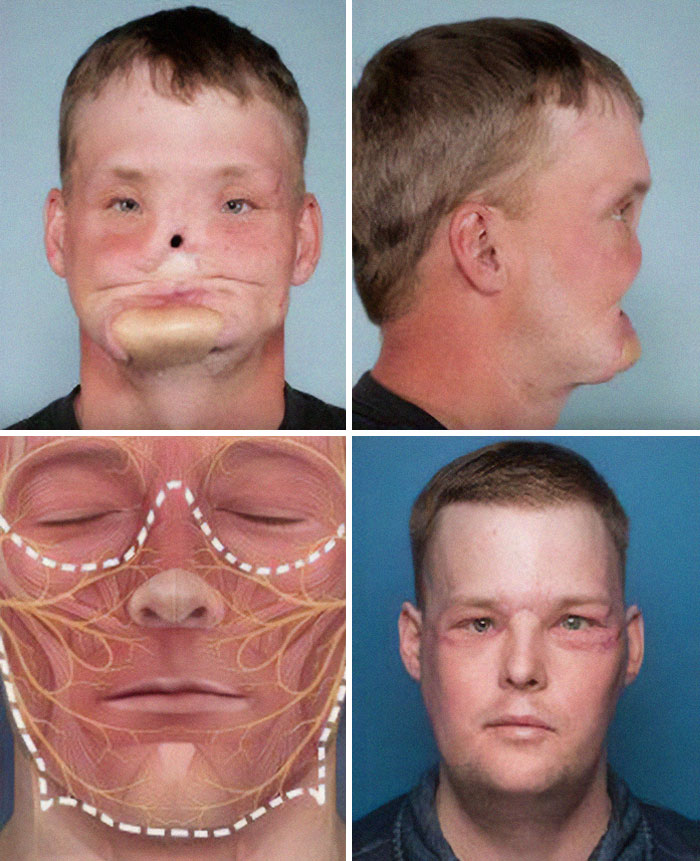

Incredible Well Performed Face Transplant